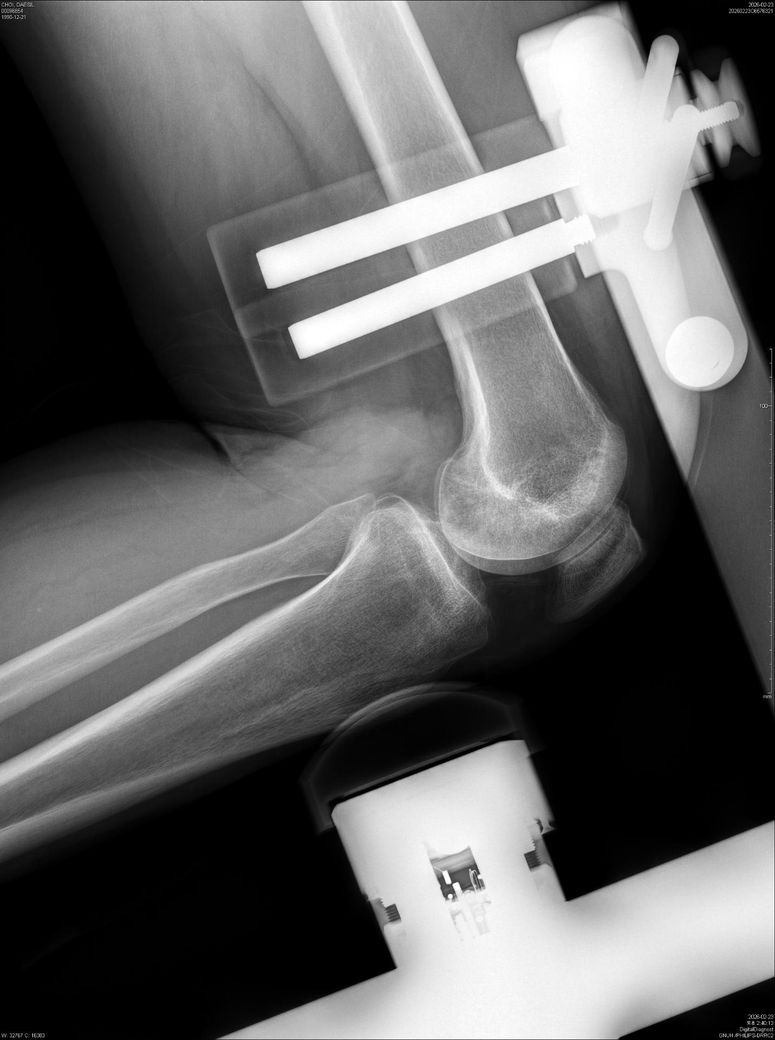

• 2번 째 사진

이 X-ray는 뼈 정렬·고정물 위치만 볼 수 있어, “무릎 동요도(십자인대 안정성)”는 판단할 수 없습니다.

동요도는 Lachman, Pivot shift 같은 이학적 검사나 MRI로 확인해야 합니다.

단순 엑스레이 사진만으로는 무릎 동요도를 측정하기 어렵습니다.

전문 장비를 이용한 검사나 스트레스 엑스레이등을 이용한 평가를 통해 확인하시는 것을 추천드립니다.